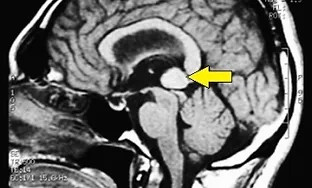

Scenari diagnostici ricorrenti osservati nel Masticationpedia Network (non singoli case report). Tutti i Network abilitati impiegano tecnologie e metodologia neurofisiologiche che permettono diagnosi precoci ed esatte di patologie che mimano sintomatologie odontoiatriche quali i Disordini Temporomandibolari ed i Dolori Orofacciali che a volte celano danni organici neurologici e sistemici. Inoltre il know how acquisito permette un controllo ed una finalizzazione dei trattamenti ortodontici, protesici ed implantoprotesici ottimizzati alle risposte neurofisiologiche trigeminali e non soltanto riferiti a parametri di forma ed estetica.